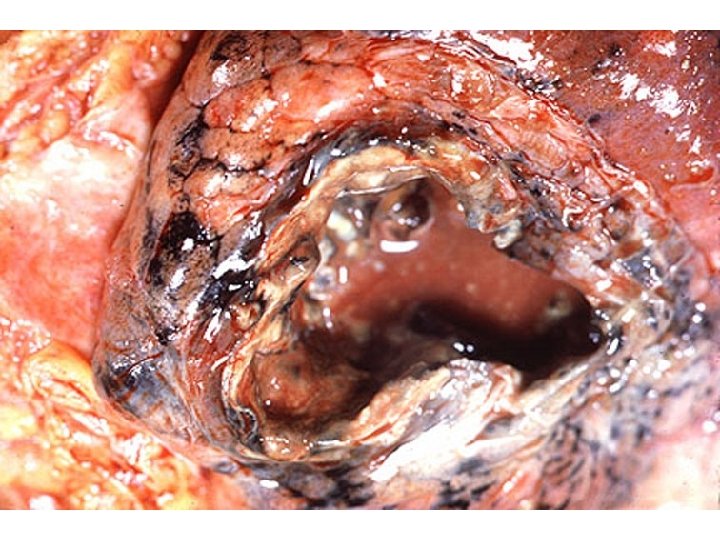

Hole Wall Lumen Content Cavity